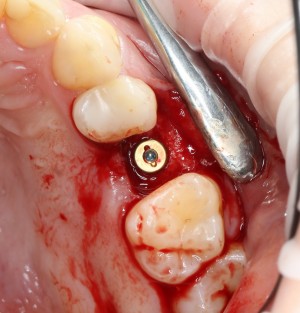

Вот исходная клиническая картинка:

К сожалению, попытка вылечить зуб эндодонтически и восстановить с помощью вкладки/коронки потерпела неудачу. Поэтому приходится его удалять.

Первое, с чего начинается удаление зуба — это разрез. С помощью скальпеля и периотома отделяется круговая связка зуба. Конкретно в этом случае важно еще увидеть границы лунки, чтобы понять пределы аугментации:

Ну и, зуб проще удалить, если ты видишь, что от него осталось. Что мы и делаем:

Вместе с зубом удаляется прикорневая гранулема. После того, как из лунки удалены все патологически измененные ткани, можно подумать о том, как сохранить объемы альвеолярного гребня в этом участке для будущей имплантации.